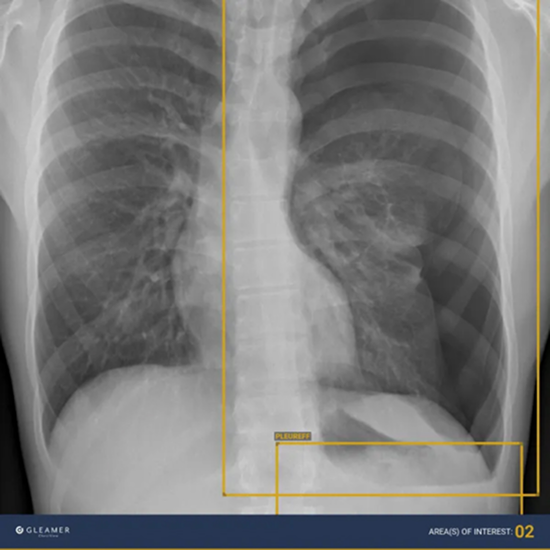

With the help of ChestView, the detection of urgent findings such as pneumothorax, pleural effusion, and consolidation, as well as early cancer indicators like nodules and mediastinal masses can be accelerated and improved.

It was co-developed with AP-HP and is based on a robust database, which was partly cross-referenced with CT-scans.

Gleamers study was able to show a significant increase in sensitivity for all anomalies.

ChestView promotes prioritization through a unique design that combines essential findings with high sensitivity, thereby assisting in patient triage.